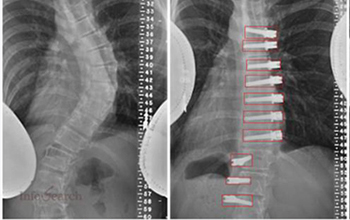

Infosearch collaborated with a medical and educational oriented organization to provide high-accuracy annotation services their applications. The project aimed at annotating the components of the human eye and surgical equipment as key points, which could be further used in medical practice, training clinical assistants, analyzing medical images, and creating healthcare AI models.

Infosearch offered end-to-end services of key point annotation, user-friendly to healthcare needs. The scope of work included:

Infosearch put trained annotation specialists who were exposed to healthcare datasets into place, using annotation manuals and medical reference materials.

In this case study, Infosearch is depicted as having the ability to provide domain-specific healthcare annotation services, which are based on medical knowledge and strong quality procedures. The effective annotation of the eye anatomy and surgical equipment parts supports the role of Infosearch as a reliable partner in healthcare data and analytics support.